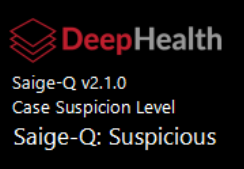

Support DeepHealth Density SR Object

The viewer supports the DeepHealth Saige-Density SR objects, displaying the case density score in the CAD header and, optionally, in the overlay data using the Breast Composition info tag.

Suspicion level indicated in DeepHealth stack ruler icons

DeepHealth CAD suspicion levels are indicated in the finding icon in the stack ruler. One to three lines indicate low, medium and high suspicion levels, respectively. No line indicates no suspicion level defined in the CAD object. Additionally, if the CAD object defines a color for the finding markers, the color is applied to the graphics in the image and stack ruler. This feature can be disabled from the Use color for CAD markers setting on the Options/Presentation States/Mammography CAD SR settings page.

Support for DeepHealth Saige-Q SR

Support for DeepHealth Saige-Q SR objects has been added. The triage header displays the algorithm name and version, and the case assessment type and value.